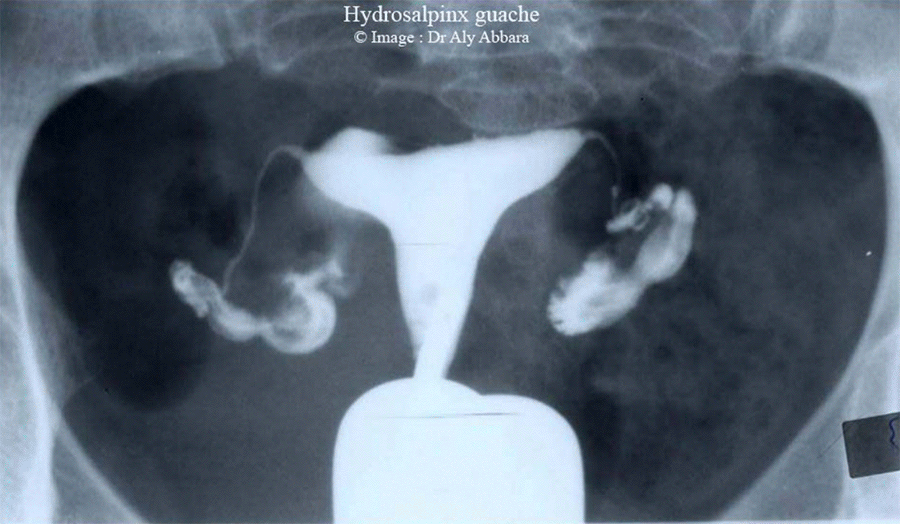

- L'hydrosalpinx :

- L'obturation complète du pavillon de la portion distale de la trompe utérine et la persistance d'exsudation séreuse dans la lumière tubaire sont à l'origine de la constitution d'une collection séreuse intra-tubaire appelée " hydrosalpinx " qui s'exprime radiologiquement par l'image d'une forte dilatation tubaire permettant l'introduction d'une quantité abondante de liquide de contraste. Celui-ci se mêle facilement et de façon homogène à la sérosité de la trompe dont il opacifie parfaitement la cavité

- L'obturation complète au pavillon qui caractérise l'hydrosalpinx se traduit radiologiquement sur le cliché de contrôle tardif par la rétention totale du produit de contraste au sein de la trompe avec absence de tout passage péritonéal.

- L'hydrosalpinx peut s'accompagner d'amincissement et d'importante altération des parois tubaires qui se manifestent radiologiquement par la disparition des plis muqueux endotubaires avec la constatation d'une forte ectasie ampullaire avec vallonnements ou dilatations en cornemuse visibles sur les clichés de face et de profil.